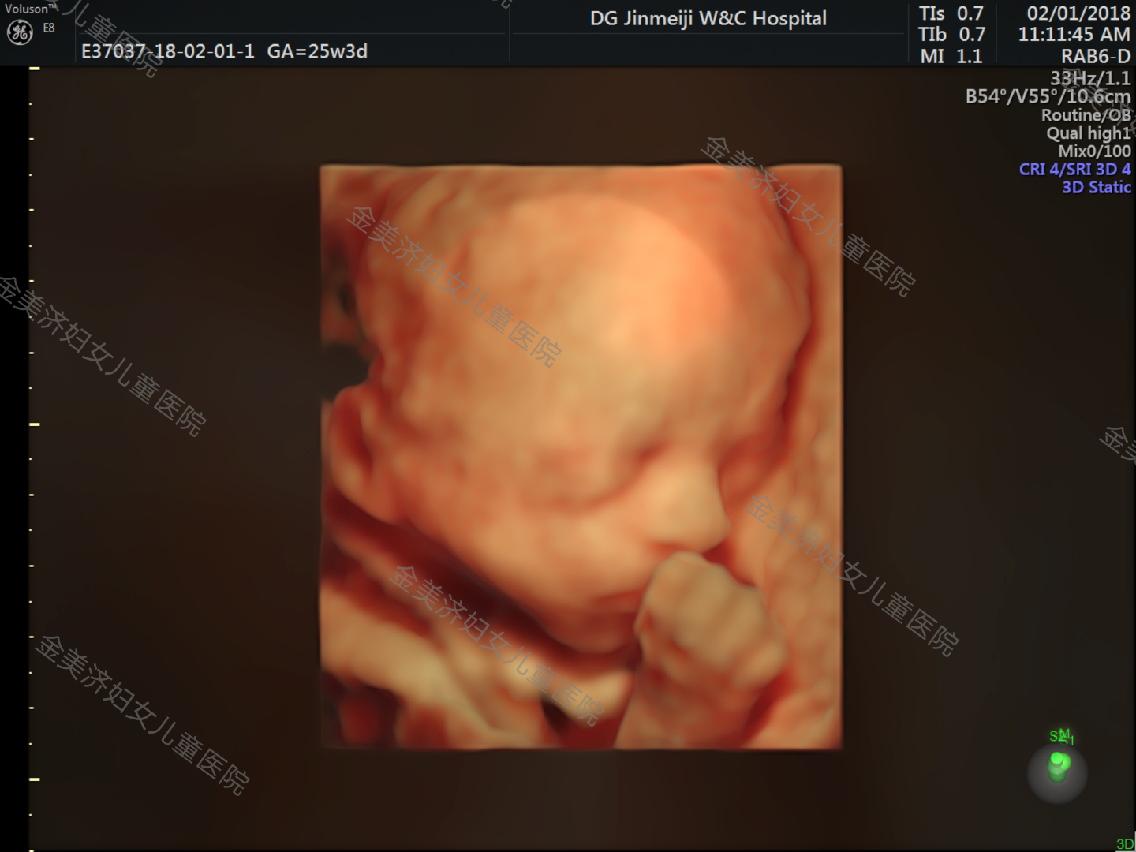

金美济妇女儿童医院采用的是GE-E8彩超,是目前国际上最为高端的四维彩超系列产品之一,被誉为“神奇彩超”,是筛查胎儿畸形的尖端设备。GE-E8彩超能显著提高图像的质量,最大限度的提高医生对于诊断的准确性和真实性。

- 显示屏可以看到宫内情况,林主任在旁边讲解,孕妈和家属可以清晰看到宝宝的情况;

- 拥有25年超声经验的专家,在系统超声诊断与鉴别方面技术高超,检查严谨细致;